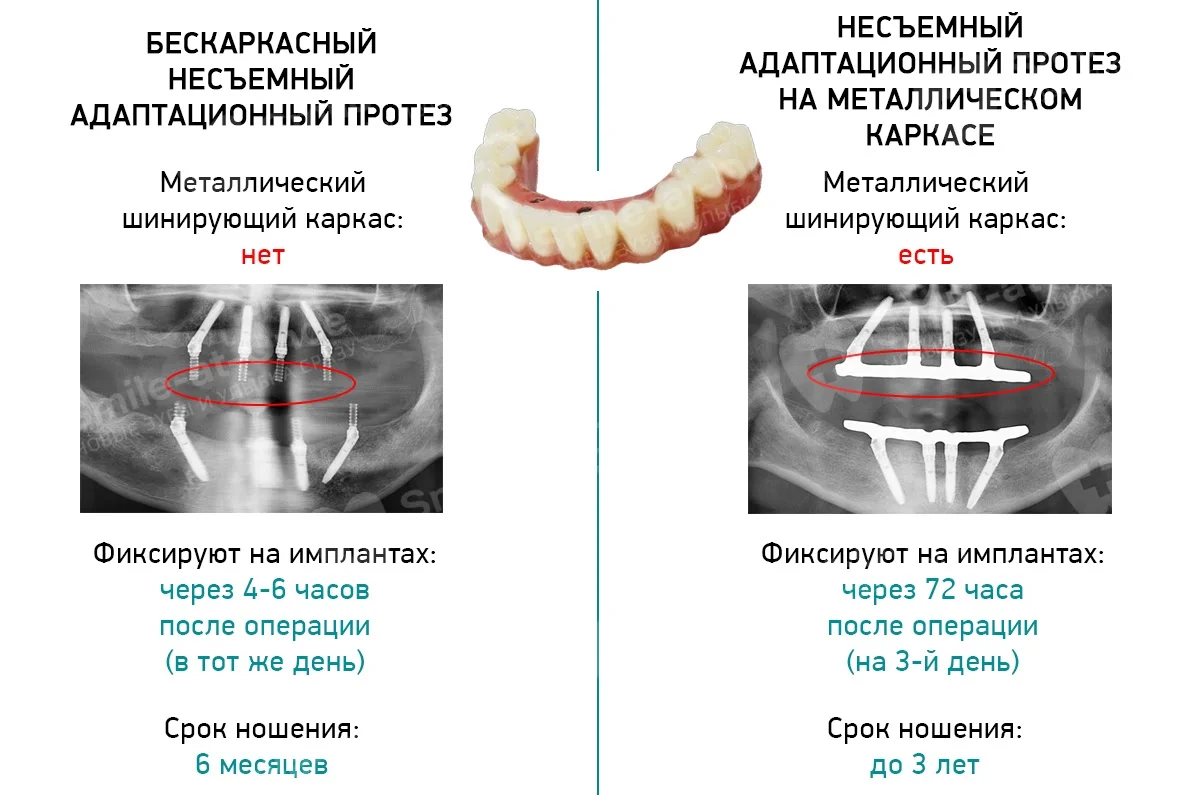

Пошаговое руководство по установке съёмного протеза на импланты